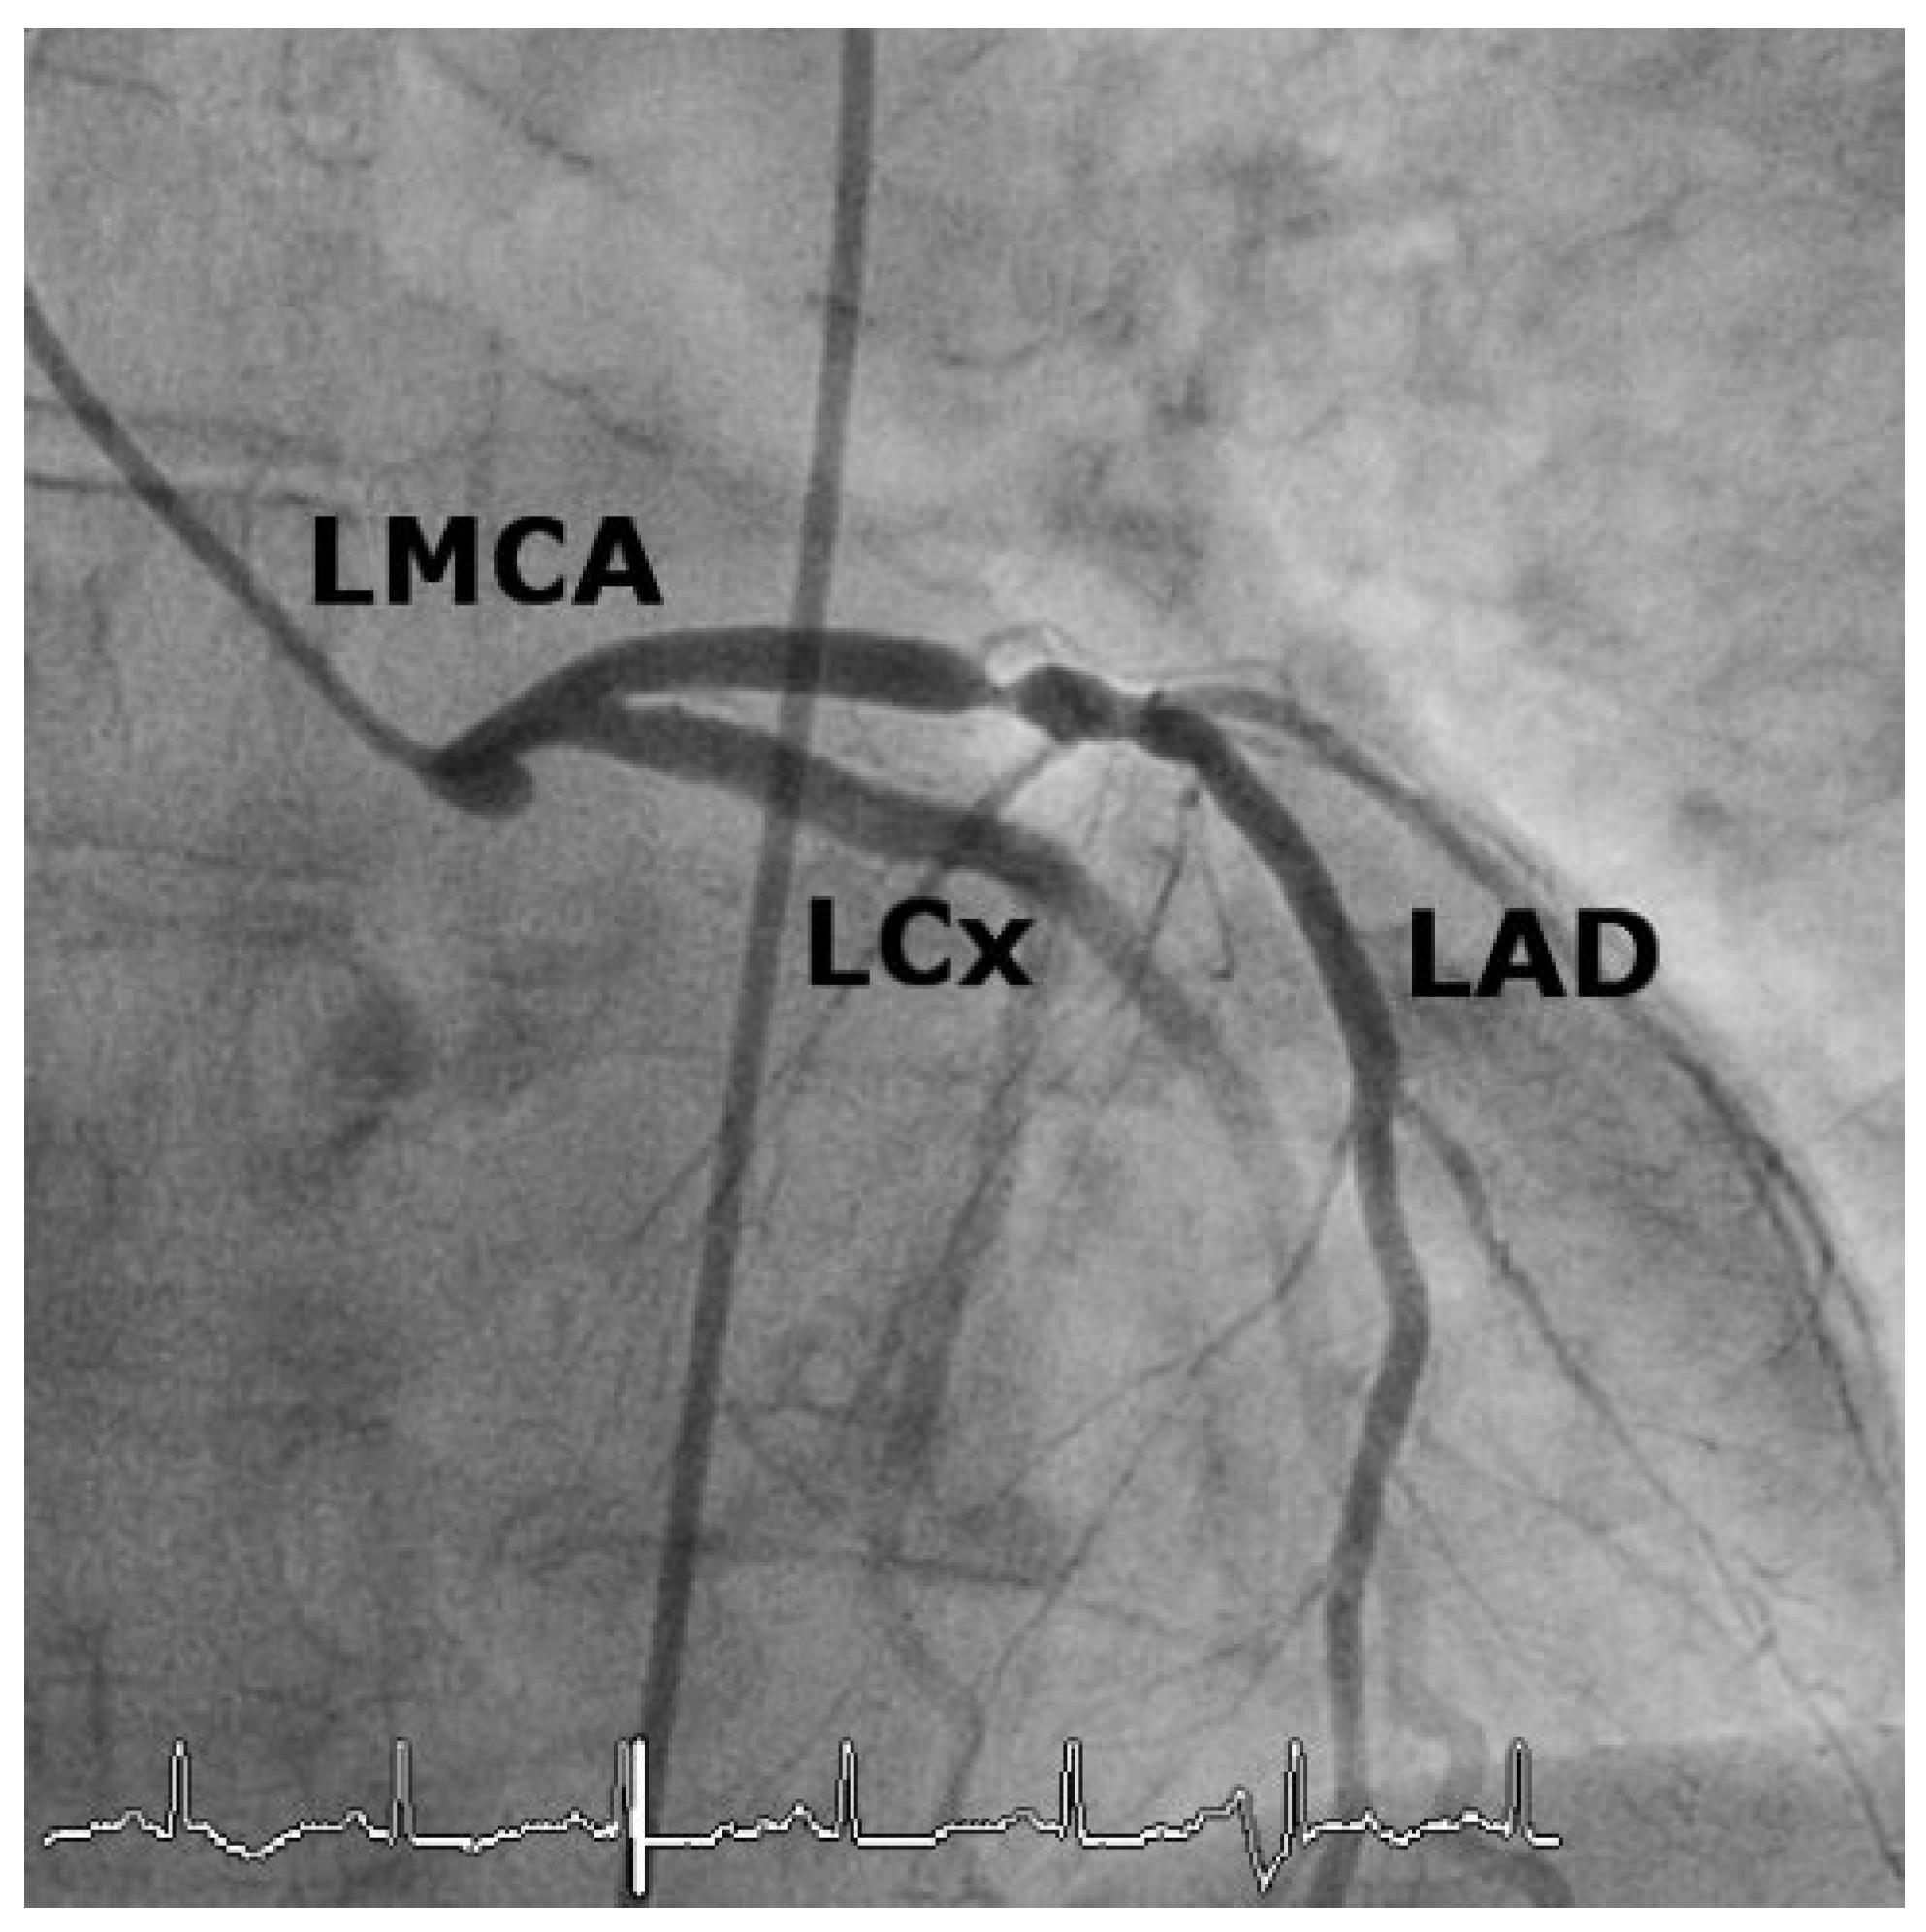

Case 1